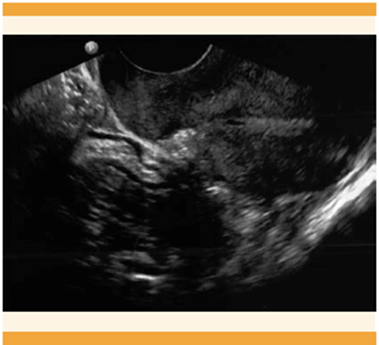

Acudió a la consulta externa de Ginecología debido a un dolor pélvico 7-10 en la escala visual análoga del dolor (EVA), con sangrados menstruales regulares aumentados en volumen y dos intentos fallidos de extracción del DIU en un consultorio. En la exploración física el abdomen se palpó blando, depresible, doloroso a la palpación profunda, el útero no delimitado, sin masas palpables. En la especuloscopia no se observaron los hilos del DIU, sin huellas de sangrado. El estado hemodinámico de la paciente era estable, sin datos de irritación peritoneal. La radiografía abdominopélvica anteroposterior evidenció el DIU en el hueco pélvico izquierdo (Figura 1). El ultrasonido endovaginal el útero se observó en retroflexión de 68 x 37 x 47 mm. El endometrio trilaminar, los anexos derechos normales, al igual que el ovario izquierdo. El fondo de saco sin datos de líquido libre (Figura 2). Para precisar la ubicación del dispositivo se practicó la histeroscopia de consultorio en la que se visualizó el área de granulación en la cara anterior derecha, probable falsa vía. Se corroboró la ausencia del DIU en la cavidad (Figura 3). La TAC simple y contrastada reportó al útero inclinado hacia la izquierda, con el dispositivo intrauterino en la trompa uterina izquierda. Figura 4

Figura 1 Imagen sonográfica con útero en retroflexión, con fondo de saco sin datos de líquido libre.